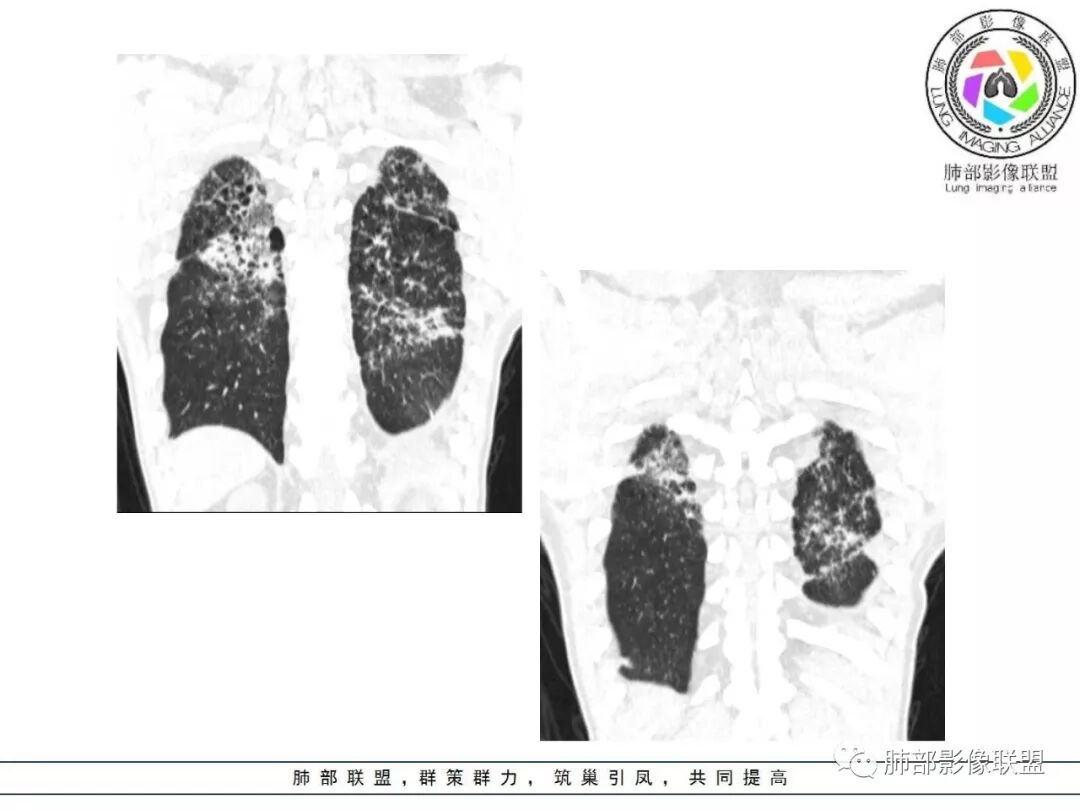

双肺间质性病变,中央间质增厚,胸膜下间质增厚,左侧胸膜肥厚,胸廓变小,肋间隙变窄。

胸部CT:两肺弥漫病灶,磨玻璃影,少许实变,部分累及胸膜,磨玻璃区可见囊?少许胸腔积液,两肺可见结节,支气管血管束增粗,小叶间隔增厚,支气管走形有扭曲扩张,可见纤维化。气肿、大泡。考虑:感染性病变,PCP?查下HIV,CD4,G等。鉴别结核、结缔组织病肺浸润。

患者中年男性,发热1月,体温38℃-39℃,峰值40℃,无畏寒、寒战,伴黄痰,CRP升高明显,降钙素原稍升高,血沉、血糖正常。胸部CT:两肺弥漫病变,磨玻璃影+点片渗出,部分累及胸膜,磨玻璃区边界清楚,少许胸腔积液,两肺支气管血管束增粗,小叶间隔增厚,部分支气管走形有扭曲扩张,可见肺气肿、右肺尖肺大泡及部分纤维化改变。综合考虑:感染性病变。结核或PCP可能性大,鉴别风湿免疫、结缔组织疾病肺浸润和腺癌等恶性病变。

胸部CT:两肺弥漫病灶,中央间质分布为主,部分位于胸膜及叶间裂旁,磨玻璃影,斑片影,部分实性结节,肺气囊,支气管血管束增粗,小叶间隔增厚,叶间裂不均匀增厚,支气管走形有扭曲扩张,可见纤维化、气肿、大泡。考虑:LIP加MALT。鉴别PLCH、PCP、结核、结缔组织病肺浸润。

双肺弥漫性病变,多发磨玻璃密度及小叶间隔增厚,大部分沿支气管血管束分布,伴支气管轻度扩张,以午后及晚上发热为主,考虑感染性病变,间质性结核可能大,另双肺多发肺气囊,LIP待排

病变一般沿血管支气管束分布或小叶分布,一般上肺多于下肺(这与常见继发性肺结核分布相若)。

2. 肺气肿背景(小叶中心性肺气肿);双肺多发病灶整体沿血管支气管束及胸膜下分布,以上叶及下叶背段分布为主,有实变及GGO,边界清楚,有树芽,小叶间隔及中央间质增厚,叶间裂见到多发结节,部分支气管不规则牵拉扩张,提示病灶纤维化明显,结合临床病史,考虑病灶为间质性感染,肺门及纵隔内有钙化淋巴结,小叶间隔结节,考虑淋巴道增值性疾病可能,综合常规要怀疑间质性肺结核。